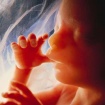

11. týden